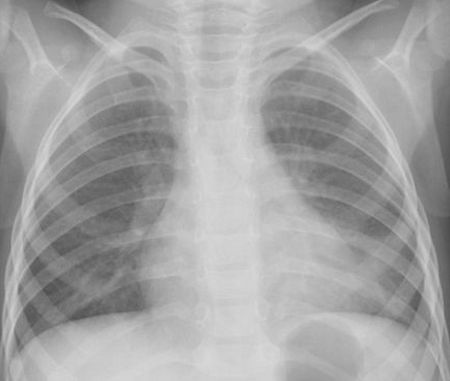

![[31]](https://www.otadragon.jp/cms/wp-content/uploads/2021/11/ukearly-500x438.jpg)

CRP 1.9mg/dl WBC 13,100 尿中肺炎球菌抗原陰性